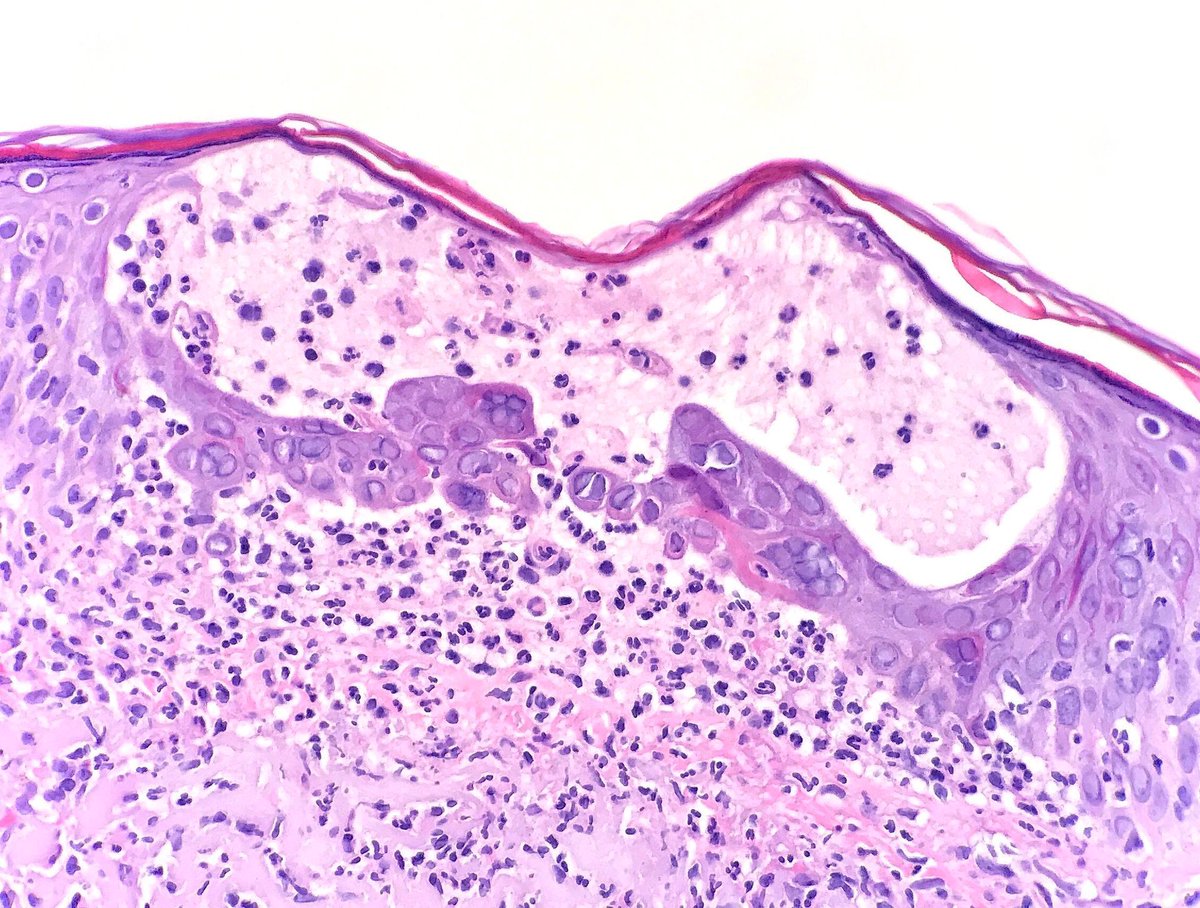

WSI digital slides: kikoxp.com/posts/21727

Immunostains: kikoxp.com/posts/21729